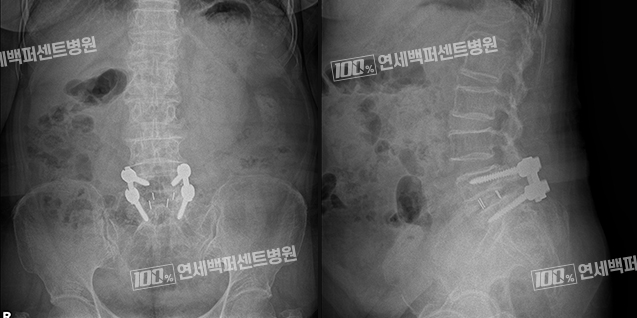

척추유합술

허리뼈가 반 이상 밀려 나오면서 허리통증과 하지방사통이 심한 경우는 처음부터 수술적 치료를 선택하는 것이 좋습니다.

척추유합술은 척추뼈 사이의 추간판을 제거하고 빈 공간에 뼛조각과 케이지[인공디스크]를 삽입한 뒤

수술용 나사를 이용해 전위를 고정하고 척추뼈 사이를 고정하는 수술

입니다.

척추전방전위증 치료 Before & After

치료 전

척추 유합술 후